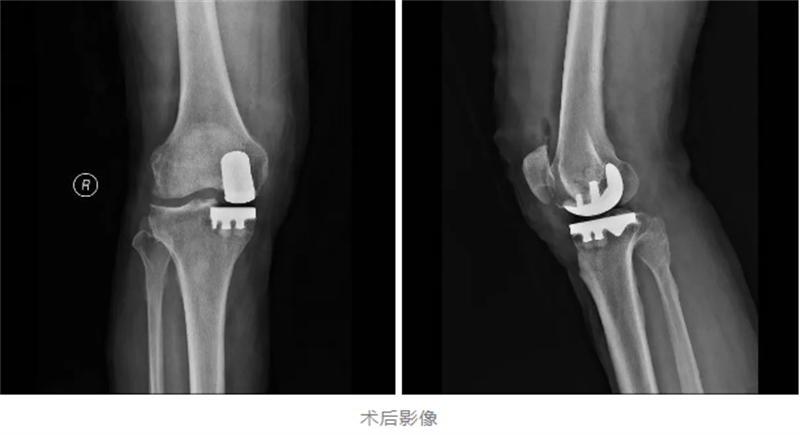

為確保手術安全與術后快速康復,關節骨病科與麻醉科展開深度協作,精心制定了個性化的麻醉方案和手術計劃。手術中,采用了“超聲引導下區域神經阻滯”加“全麻”的方式,既確保了手術過程中的無痛和舒適,又減少了麻醉對患者的副作用。手術當天,多學科團隊配合默契,僅用1小時便順利完成了置換手術。

麻醉科主任余相地博士介紹,本次手術創新采用“無管化管理”模式:不插尿管、傷口不放置引流管,并嚴格控制止血帶使用時間,從細節入手將創傷與并發癥風險降低。

患者麻醉蘇醒后身體狀態良好,既無頭暈惡心等不適反應,下肢肌力也保持正常,手術切口痛感輕微。令人欣喜的是,在醫護人員的全程保障下,患者術后就能下地行走,自行走出手術室,借助助行器穩穩地返回了病房。